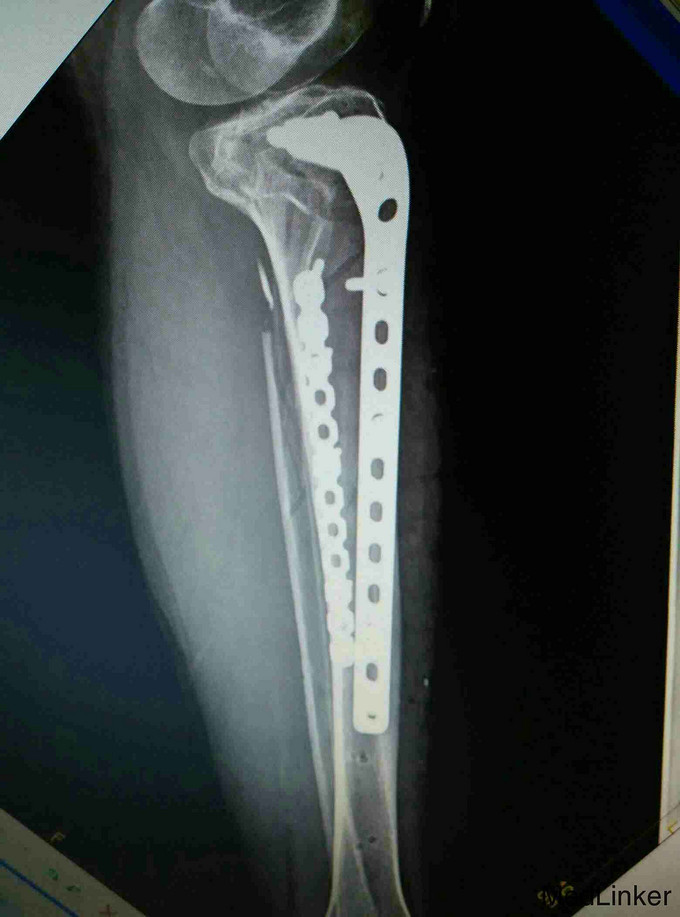

考虑为筋膜室综合征,予急诊行切开减压,考虑一期骨折复位内固定手术风险高,则行骨折端外固定架固定,同时VCD引流,待局部肿胀减轻,局部无明显张力,伤口无炎性反应后,二期行开放复位钢板固定术。

术后恢复良好,伤口正常愈合,功能佳。 讨论:小腿骨折常引起筋膜室综合征,应注意观察,特别是小腿上段骨折更容易引起筋膜室综合征,因为其血运好,出血多,如果发现筋膜室综合征或可疑筋膜室综合征,都要毫不犹豫的切开,不建议行一起的骨折端复位内固定,感染等风险较大,可暂时外固定架固定,同时VSD引流,可以减少换药及感染概率。术后7到10天局部肿胀减轻,无感染迹象后再行切开复位钢板固定术。